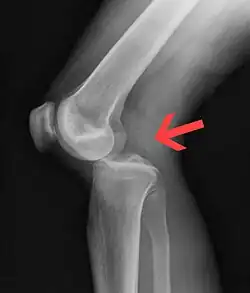

![]() | |

| Plain lateral X-ray of the left knee showing a posterior knee dislocation[1] | |